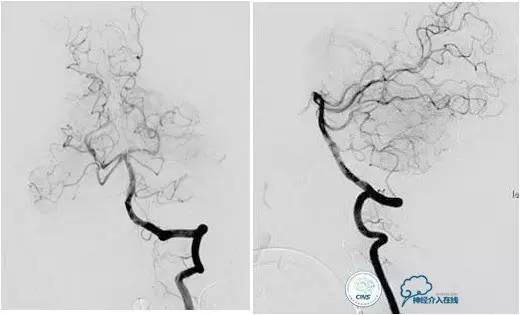

乙状窦区的DAVF,供血动脉细小,静脉引流道通畅。

同侧颈内静脉试图进入引流静脉,但是由于角度问题非常困难。

从对侧颈内静脉绕路进入引流静脉。

Sceptor球囊导管到达静脉内,充盈球囊,让后注入Onyx。

术后造影提示DAVF治愈。